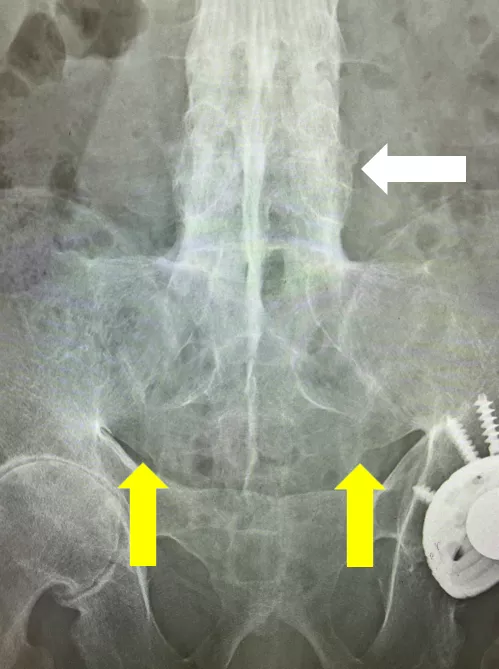

若年男性に発症した、運動により改善して安静により改善しない3か月以上持続する炎症性腰背部痛の所見と血清反応陰性、CRPの上昇より脊椎関節炎を疑った。単純X線では両側仙腸関節に関節裂隙全体の強直を認めgrade4の仙腸関節炎の所見であった(写真1)。また、同写真で腰椎の椎体辺縁に沿った硬化像も認めた(写真1)。追加で行った頸椎(写真2)、胸椎(写真3)、腰椎(写真4)単純X線の側面像では全脊椎の強直(竹様脊椎、bamboo spine)を認めた。以上より強直性脊椎炎と診断した。

写真2 単純X線 頸椎側面像

椎体辺縁に沿った硬化像を認める